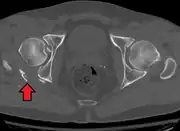

Axial CT image (viewed on bone windows) of a complex comminuted left acetabular fracture involving both anterior and posterior columns.

In all cases, CT scan can assist in identifying impacted bone pieces, which may be found within the joint, and MRI may be done to identify the extent of potential injury to the sciatic nerve.